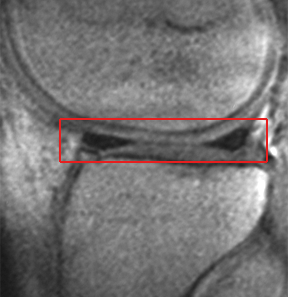

Review of MRI (right) - this 'slice' of MRI scan from the side view of the knee revealed an intact medial meniscus (the two dark triangles within the red box are cross sections of the front and back parts of the meniscus), damage to the articular cartilage surface, and anterior arthrofibrosis.